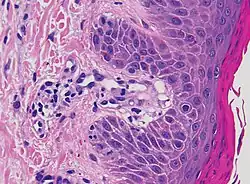

| Prevesicular stage of bullous pemphigoid | Image at right shows influx of inflammatory cells including eosinophils and neutrophils in the dermis (solid arrow) and blister cavity (dashed arrows), and deposition of fibrin (asterisks).[15] However, the diagnosis of bullous pemphigoid consist of at least 2 positive results out of 3 criteria:[19]

|